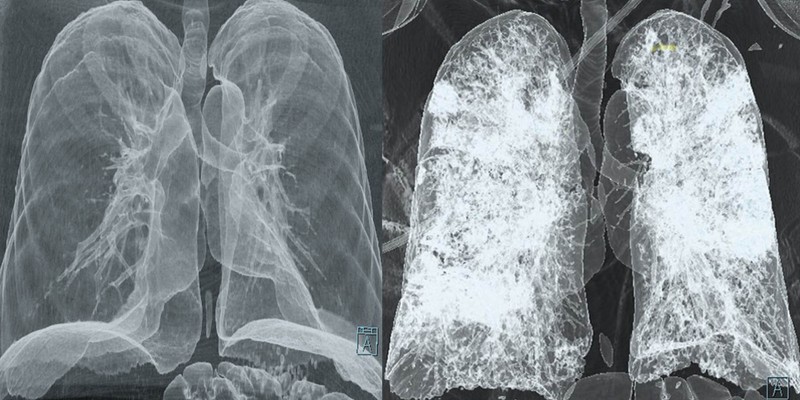

A tüdő CT (komputertomográfia) egy speciális képalkotó vizsgálat, amely részletes keresztmetszeti képeket készít a tüdőről és a környező struktúrákról. Ez a vizsgálat jóval részletesebb képet ad, mint egy hagyományos mellkasi röntgen, így pontosabb diagnózist tesz lehetővé számos tüdőbetegség esetén.